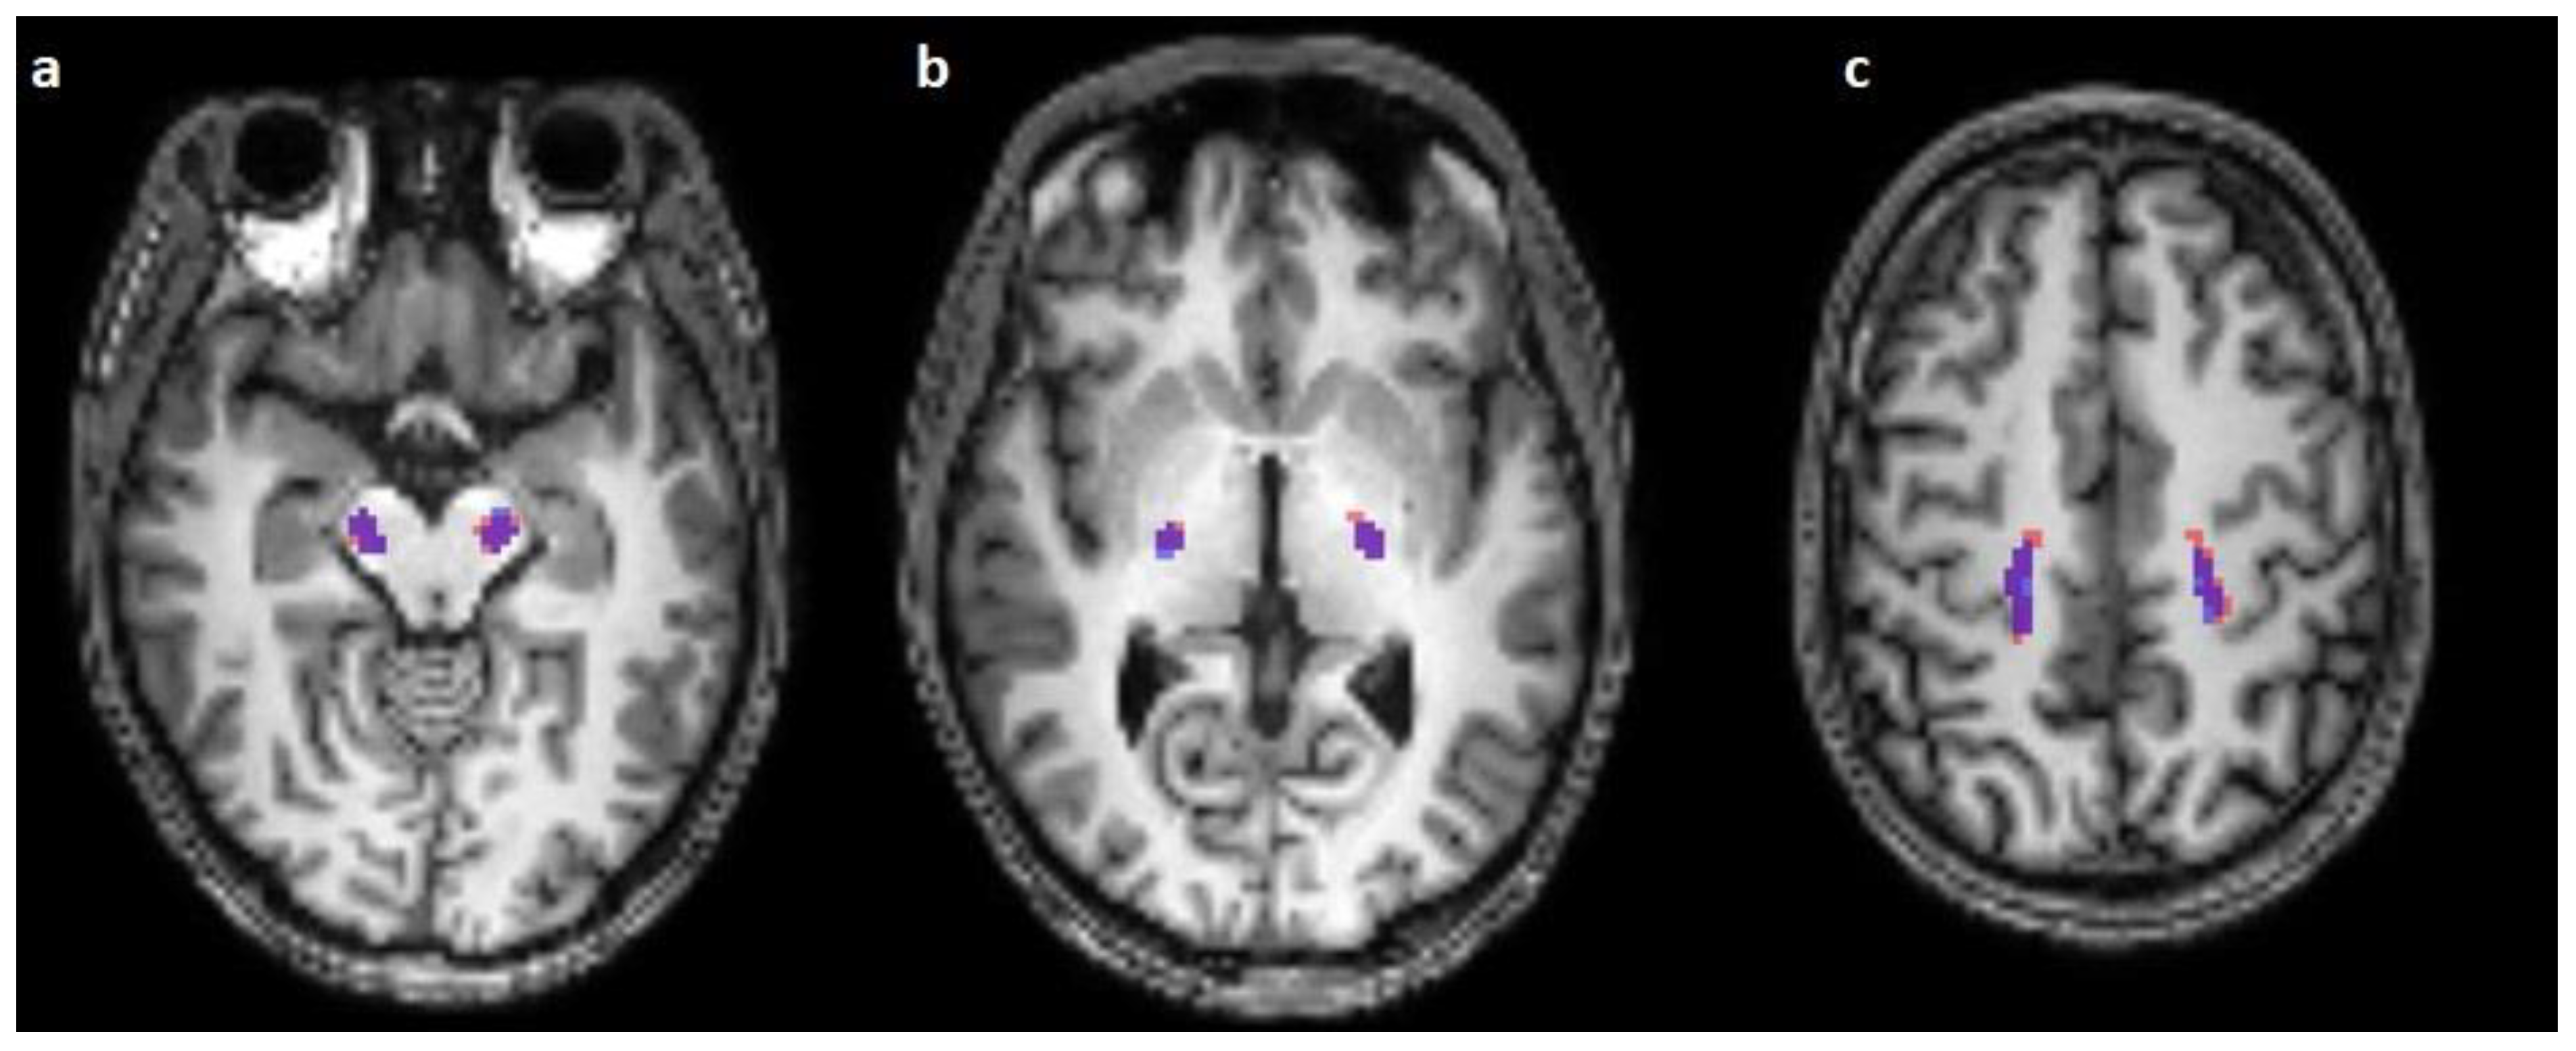

The corticospinal tract traversed the ventral part of the pons in 100/100 cases (100%), traversed the middle-third of the crus cerebri of the mesencephalon in 100/100 cases (100%), traversed the posterior limb of the internal capsule in 100/100 cases (100%), and originated from the medial part of the precentral gyrus in 89/100 cases (89%) (Figure 1, Figure 2 and Figure 3).

Figure 1.

Comparison of the predicted (blue) and reconstructed (red) course of the corticospinal tract on horizontal T1-weighted images in the mesencephalon (a), the crus posterior of the internal capsule (b), and in the centrum semiovale (c).